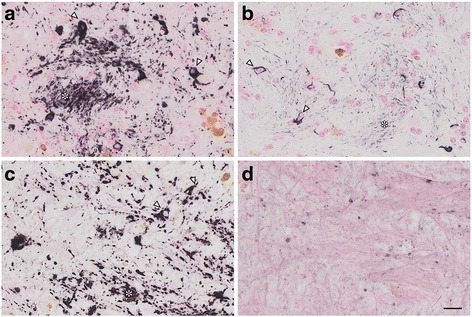

In the GP, AT8 immunoreactivity (IR) was found in fiber bundles (asterisk, c) and small round cells, likely to be oligodendroglia (arrowheads, c. See Fig. 4 for more details). AT8 IR was also abundant in the white matter in the temporal lobe (a, asterisk) and the hippocampus (asterisks in a and d). Higher magnification of the hippocampal white matter (e) identified AT8-positive oligodendroglia-like cells (arrowheads, e) and fibers (asterisks, e). Adjacent hippocampal slices demonstrated 4R tau (RD4, Fig. 1f) IR in pyramidal neurons (arrow, Fig. 1f) and in the hippocampal white matter (asterisk, Fig. 1f). Because 3R tau IR was absent in these AT8/RD4-positive lesions (data not shown), their staining profile was different from that of human AD, which is immunopositive for both 3R and 4R tau [ref. 11, ref. 12]. At higher magnifications, AT8 (Fig. 2a) and RD4 (Fig. 2b) tau immunoreactivity was diffuse and granular in the neuronal cytoplasm and dendrites, and rarely organized into NFTs. Argyrophilia with Gallyas silver impregnation was quite limited (Fig. 2c, arrowhead) and they were not argyrophilic with Campbell-Switzer silver impregnation (data not shown). The scarcity of NTFs, fibrillary structure, and Gallyas silver argyrophilia, also differs from AD pathology in the human brain (Fig. 2d, arrowheads).

We observed numerous AT8-positive processes (Fig. 3a, dark purple, arrowheads), independent of Aβ (Fig. 3a, brown, asterisk) in the temporal cortex. Similar structures in the same area were positive exclusively for RD4 (Fig. 3b) and oriented around blood vessels (Fig. 3b, arrows). Thorn-shaped astrocytes or granular/fuzzy astrocytes grouped under the umbrella of “aging-related tau astrogliopathy” were not apparent in these monkey brains [ref. 22]. AT8-positive oligodendroglia-like cells and threads were abundant in GP (Fig. 4a) and in the white matter (Fig. 1e). Both perikarya and threads of these oligodendroglia-like cells were positive for both Gallyas silver impregnation (Fig. 4b), and RD4 (Fig. 4c) in adjacent sections, but consistently negative for 3R (Fig. 4d). In summary, AT8/RD4-positive neurons were pretangle-like but their distribution was accentuated in pyramidal neurons of Ammon’s horn (Fig. 1a and f arrow) as in AD. However, AT8/RD4-positive glial cells in the hippocampal white matter (Fig. 1a, d and f asterisks) and basal ganglia were conspicuous.

In all brains examined in this study, tau-positive structures exhibited immunoreactivity for 4R, but not 3R tau. Tau-positive structures were also argyrophilic with Gallyas, but not with Campbell-Switzer silver impregnation. This cytopathology is different from that of AD, which usually exhibits immunoreactivity for both 3R and 4R tau, and argyrophilia with both Gallyas and Campbell-Switzer silver impregnations [ref. 19]. Instead, these phenotypes suggest that a PSP or CBD-like cytopathology may occur in brains of aged primates. Supporting this idea, the 4R-positive structures that we identified around blood vessel in old primates (Fig. 3b) are similar to tau-positive structures identified in tuft-shaped astrocytes in PSP and astrocytic plaques in CBD [ref. 25]. Further, we did not observe tau IR in neurites around senile plaques (Fig. 3a, asterisk), suggesting that most tau-positive structures in old primate brains may be of glial origin similar to human PSP/CBD, which are not frequent in aged human brains with AD pathologies. Moreover, these tau-positive astrocytes are morphologically different from thorn-shaped astrocytes, granular/fuzzy astrocytes grouped under the umbrella of “aging-related tau astrogliopathy [ref. 22]” Consistent with our results, Kiatipattanasakul and colleagues [ref. 26] previously described PSP-like tau deposition in neurons and glia in an aged (35 yo) albino cynomolgus monkey. They also observed Gallyas-positive glia in the basal ganglia, thalamus, brainstem and the white matter as well as NFTs in the thalamus. However, they proposed that the occurrence of PSP-like cytopathology in their monkey brain was exceptional. In our study, however, we observed similar neuronal and glial cytopathological alterations of tau in 5 out of 7 monkeys over 30 years of age (Table 2, Fig. 5), suggesting that PSP-like cytopathologies may instead represent a common aspect of aged monkey brains.

4R tau labeling and Gallyas argyrophilia were more intense in oligodendroglia-like cells in the white matter (Fig. 4b) than in neurons (Fig. 2c). In these oligodendroglia-like cells, AT8-labeled fibrils were 20–25 nm in diameter without apparent constriction (Fig. 6b), similar to those reported in tau-positive fibrils in oligodendroglia in PSP brains [ref. 27]. In contrast, in oligodendrotcytes in AD brains, mixtures of straight filaments with a diameter of 16 nm, and irregularly constricted filaments with greatest width of 30 nm have been described [ref. 28].